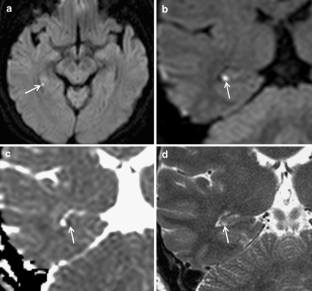

Fourteen patients had small (1–3 mm) high-signal abnormalities in the hippocampus unilaterally on DW images. One of these patients had two lesions in one hippocampus and therefore in total 15 lesions were identified: four in the hippocampal head, and 11 in the body. Eleven lesions in ten patients with available coronal images were clearly demonstrated on both coronal DW and T2-weighted images and were localized to the lateral portion of the hippocampus, corresponding to the CA1 region.

Lesions associated with TGA were localized exclusively to the lateral portion of the hippocampus corresponding to the CA1 region. This finding supports the ischemic etiology of TGA; however, the pathophysiological mechanism involved requires further study.